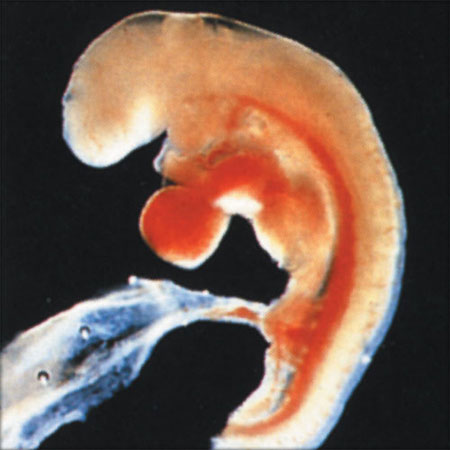

04 недеље од зачећа

од зачећа 4 недеље